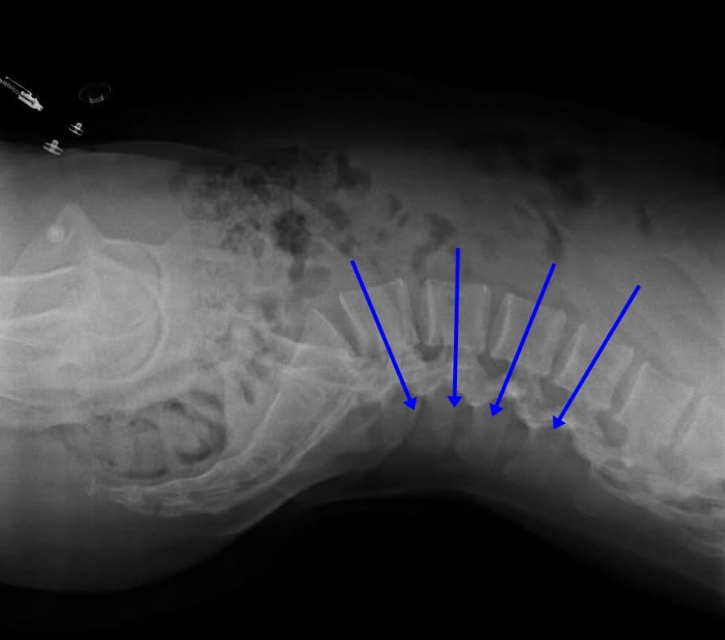

한 번쯤은 똑바로 누웠다가 허리가 뻐근하거나 아파서 다시 옆으로 돌아눕는 경험, 해보셨죠? 특히 장시간 누워 있을 때 허리 아래쪽이 당기듯 아픈 느낌이 드는 분들 많을 거예요. 그 이유 중 하나는 골반 전방경사 때문입니다. 골반이 앞쪽으로 기울어져 있으면, 자연스럽게 허리의 전만 곡선도 커지게 되거든요.

이 상태로 등을 바닥에 대고 누우면, 허리가 바닥과 뜨게 되고 중력의 영향으로 척추에 부하가 더 많이 걸립니다. 말 그대로 허리에 부담이 집중되는 자세가 되는 거죠. 그래서 자는 동안에도 통증이 지속되거나 심해지는 경우가 많습니다.